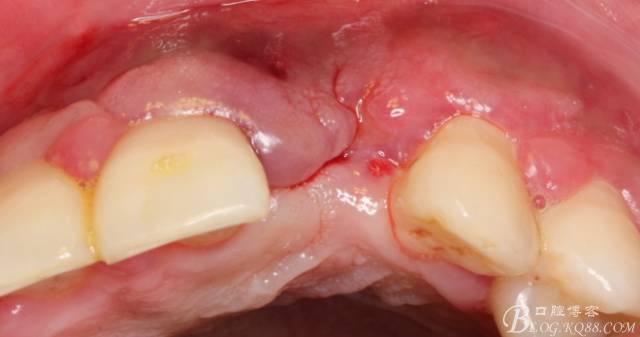

4個月后,唇側(cè)豐滿度尚可,與鄰牙之間齦乳頭完整。

保留齦乳頭翻小瓣。